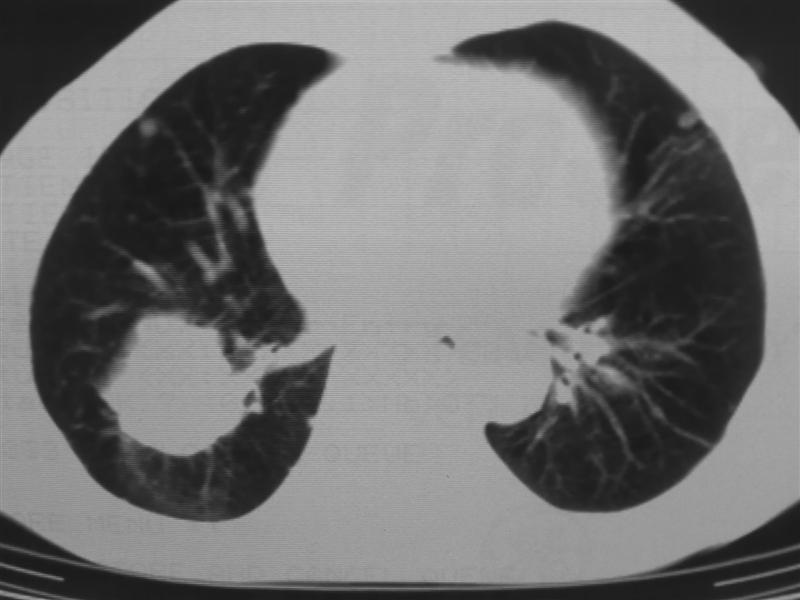

支持右下肺癌伴肺内转移

右下肺周围型肺癌伴双肺右侧叶间 胸膜及右肺门淋巴结转移

肺癌伴肺、胸膜转移

肺癌肺内转移。